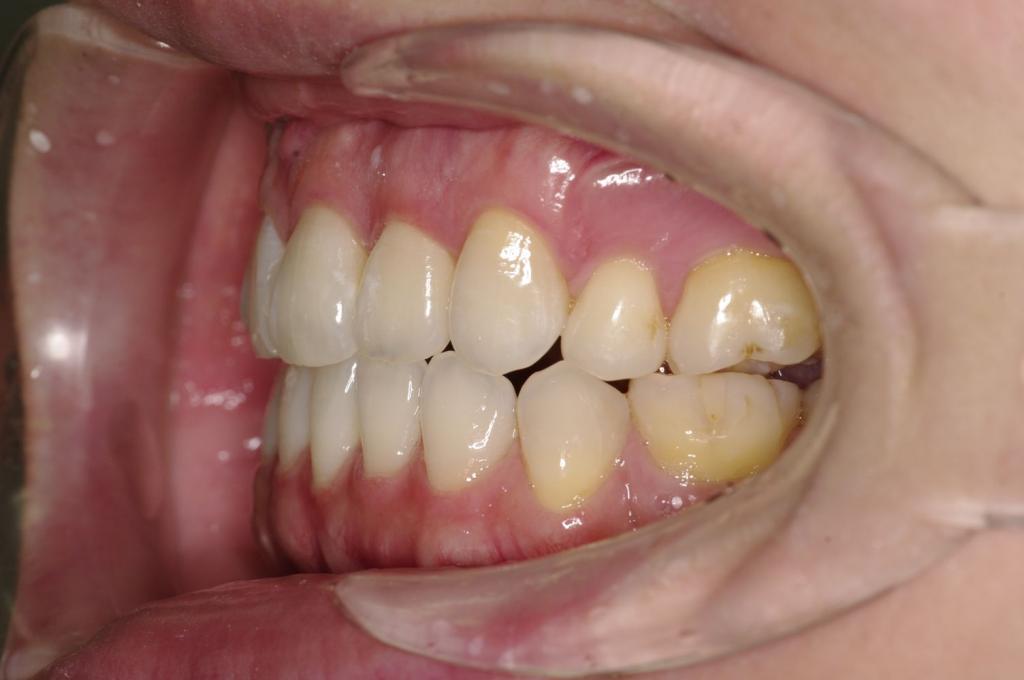

前歯、出っ歯・開咬の矯正治療

(治療期間、治療前後写真、治療方法、費用)WORKS